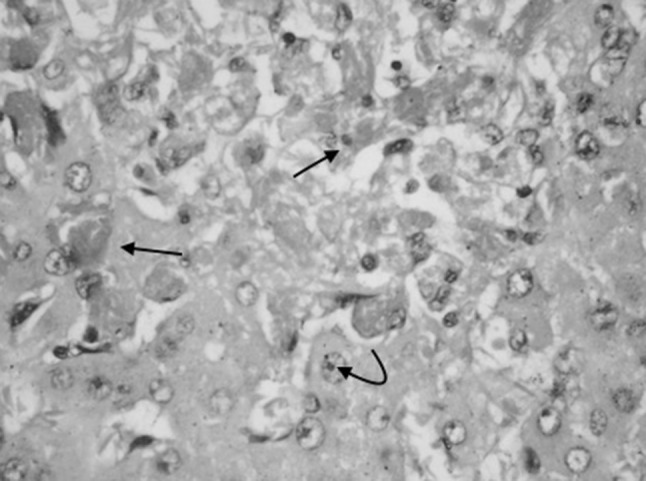

Fig. 1.

Liver biopsy of Case 3 showing dilated, congested sinusoids with sickled RBCs (arrow mark) and hepatocyte necrosis (H&E ×400)